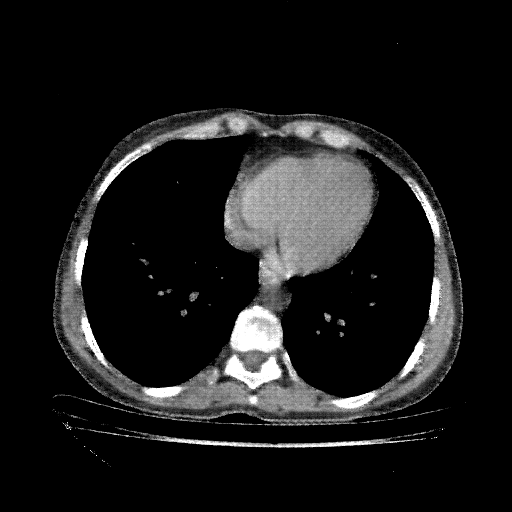

Targeted Slice 70 - Mediastinum Window Analysis (Generated vs Real Venous)

0.805

Mediastinum SSIM

38.0

Mediastinum RMSE

12.5

Mediastinum MAE

Generated VENOUS CT scan (A→B translation)

No window - Raw intensity values